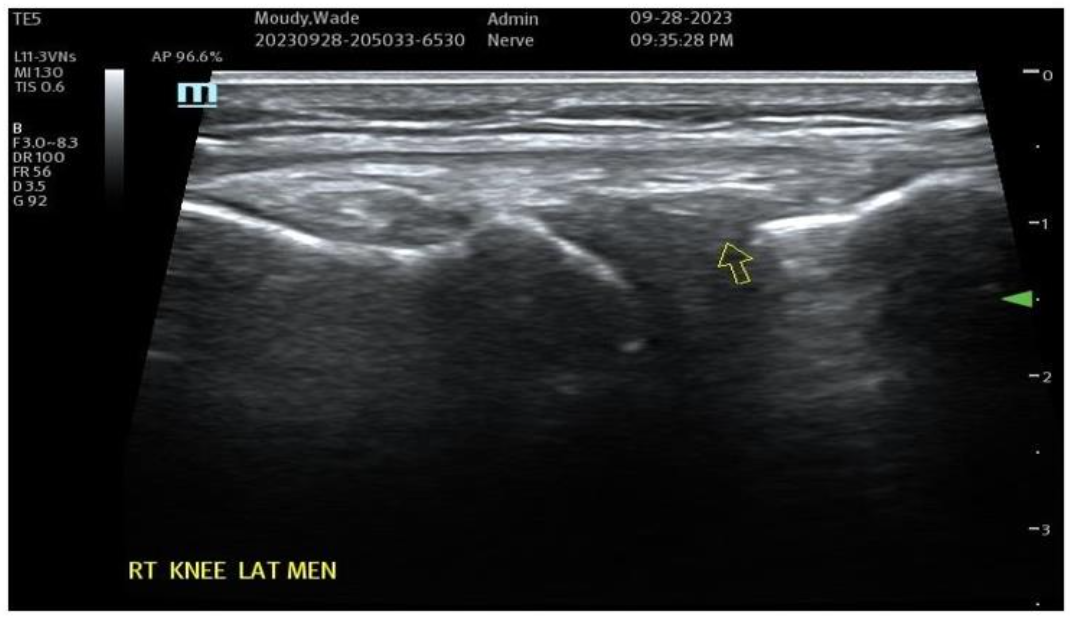

Cartilage Healing: Although Hyaline Cartilage is very slow to repair due to lack of internal vascularity, it has been shown to occur. More often the response is towards a form of fibrocartilage, which does often improve the comfort in the areas of intra-articular structure and osteoarthritis. It is also known that the addition of low hematocrit form of HD PRP in combination with the Nanofat also has impact to this process and helps with favoring a desired type of a “benign” inflammatory environment. When some blood derivatives only are utilized without Nanofat, a “flare” of inflammatory response may be encountered following such placement. This event may be significantly reduced simply by reduction of inflammatory reaction seen by modulation provided by Nanofat addition. Further, use of only blood-derivatives not only may flare, but may often require several interval treatments to provide much or long-term help.

Figure 7A: Pre-Treatment Medial Meniscal/MCL Damage and Inflammatory Changes. Figure 7B: Painful Meniscal/LCL ultrasound image outcome at 10 months BC treatment. tSVF + HD PRP (5.5X) (70% tSVF/30% HD PRP. NOTE: Improvement of lateral meniscal/LCL areas without residual pain or dysfunction.